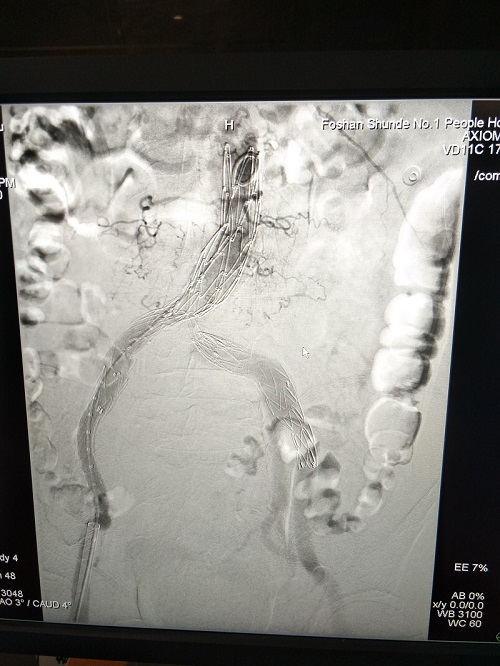

術(shù)后動(dòng)脈瘤被隔絕

病情十分危急,患者情況不適合外科治療,需要盡快介入手術(shù),但患者情況十分特殊,因?yàn)樗母怪鲃?dòng)脈長度特別短,鈣化也非常嚴(yán)重,整個(gè)華南地區(qū)都沒有適合他的更短的支架。我們多方打聽,最終找到一種一體式主體最短為70cm的新型覆膜支架適合患者,但需要從外省緊急調(diào)貨過來。在等待的過程中,通過積極的藥物治療,患者病情得到有效控制。7月6日一早,支架到貨后,醫(yī)生們立即為患者開展介入手術(shù),手術(shù)過程順利,為患者解除了這個(gè)不定時(shí)炸彈!

一體式支架操作較為復(fù)雜,但優(yōu)勢(shì)也很明顯:減少了因?yàn)榻油榷斐傻膬?nèi)漏,支架也更加不容易移位。我院心血管內(nèi)科多年來獨(dú)立完成主動(dòng)脈覆膜支架植入術(shù)數(shù)十例,救治了大量主動(dòng)脈夾層和主動(dòng)脈瘤的患者,經(jīng)驗(yàn)豐富,完成了多次高難度的手術(shù)。本例患者主動(dòng)脈360度嚴(yán)重鈣化,血管迂曲,一體式新型支架是首次操作,手術(shù)極具挑戰(zhàn)性。